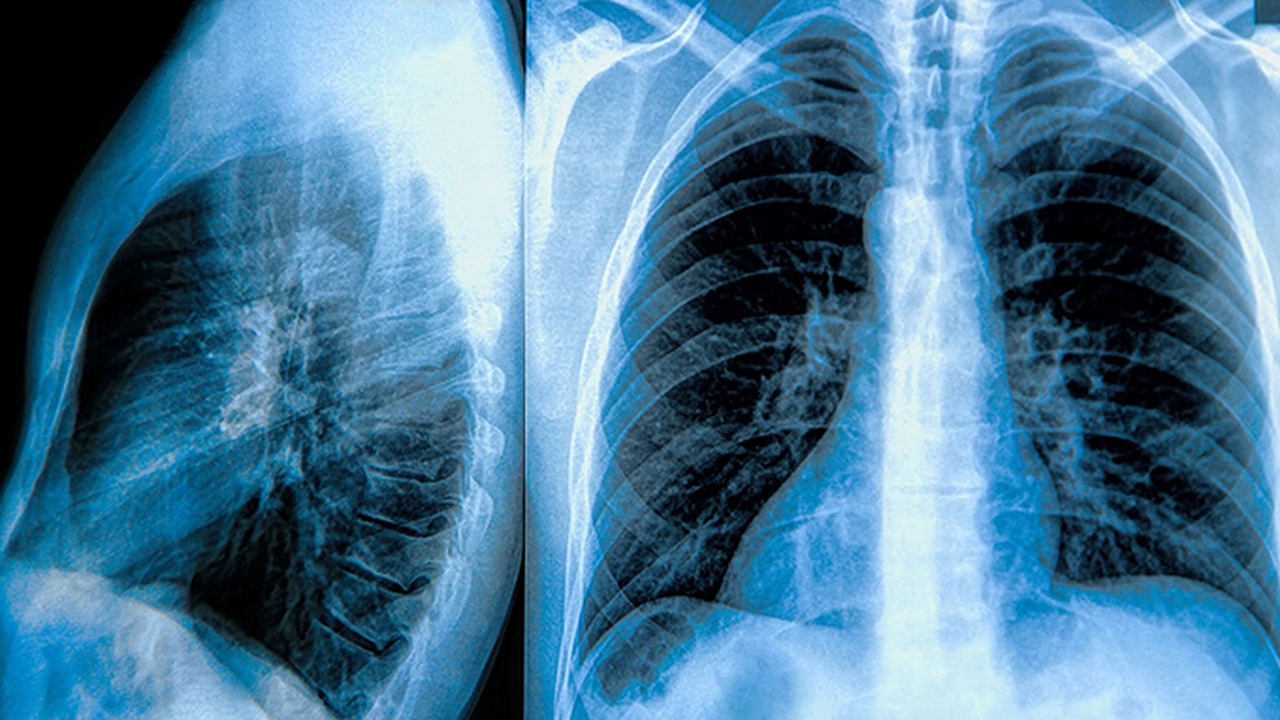

肺脓肿是由细菌感染引起的肺部化脓性炎症,常见病因包括吸入性感染、血源性感染或邻近组织感染扩散。该病典型表现为高热、咳嗽、咳大量脓臭痰,严重者可出现咯血和呼吸困难。及时规范的抗生素治疗结合引流是关键,部分病例需手术干预。